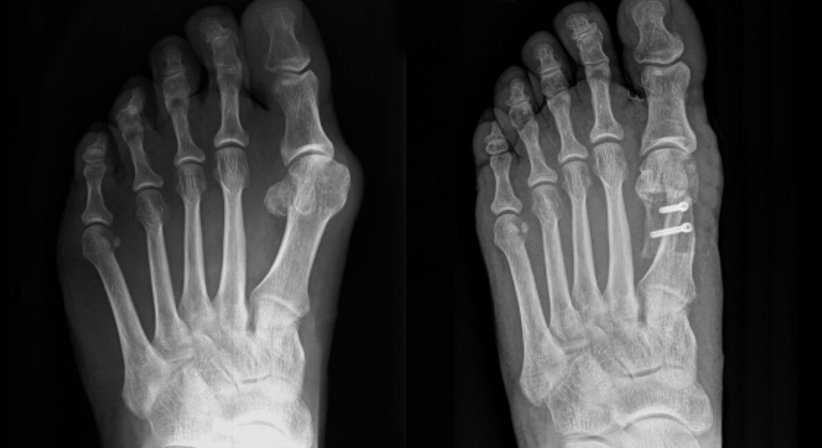

Die Hallux valgus-Operation ist ein sehr individueller Eingriff, für welchen je nach Schweregrad unterschiedlichste Operationsverfahren zur Verfügung stehen, darunter die Chevron-, die Austin- und die Scarf-Osteotomie.

Besonders wichtig für die Operationsplanung ist, dass es sich bei einem Hallux valgus stets um eine Kombination verschiedener Veränderungen im Bereich des Fußes handelt - Hautveränderungen, Schleimbeutelentzündungen, die Verdrängung der benachbarten Kleinzehen, schmerzhafte Überlastungen und andere begleitende Krankheitsprozesse werden bei der Therapieplanung ebenso berücksichtigt wie der Schweregrad der Fehlstellung und andere Faktoren. Im Rahmen der Diagnostik ist es besonders wichtig, die individuelle Situation des Patienten exakt zu erfassen - durch eine genaue Diagnostik und Analyse der Fehlstellung kann die Operation im Vorfeld sehr gut geplant und exakt an die jeweilige individuelle Ausgangssituation angepasst werden.